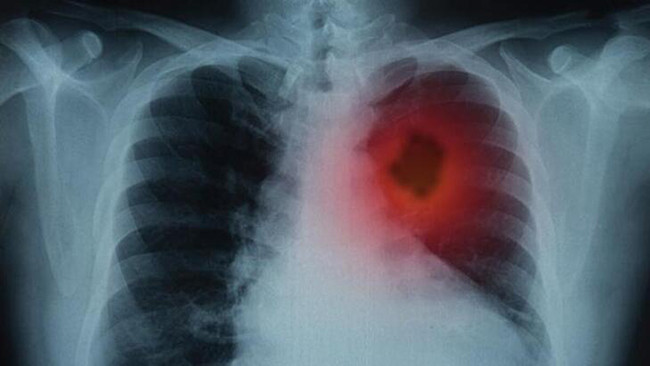

Kalp çarpıntısıDüzenli kalp çarpıntısı emboli belirtisi olabilir. Akciğerlerinizdeki bir kan pıhtısı, akciğerlerinize giden oksijen tedarikinin sınırlandırılmasına veya hatta tıkanmasına neden olabilir. Kalbin bunu telafi etmesi gerekir, bu yüzden daha hızlı, daha sert ve daha düzensiz atmaya başlar.

Göğüste ağrıDaha önce akciğer embolisi yaşayan kişiler genellikle bunun kalp krizi geçirmeye benzediğini söylüyor. Bunun nedeni, kalp krizi ağrısının akciğer embolisi ile karşılaştırılabilir olmasıdır. Aradaki fark, akciğer embolisi ağrısında sanki bıçaklanıyormuşsunuz gibi hissedersiniz ve derin nefes aldığınızda ağrı daha da kötüleşir.

Nefes darlığıAkciğerlerdeki bir emboli de nefes alma zorluğu yaşamanıza sebep verebilir. Yukarıda söylediğimiz gibi, bu kan pıhtısının oksijen kaynağı ile karışmasına neden olur. Bu semptom o kadar kötüleşebilir ki bayılmak üzereymiş gibi hissedebilirsiniz.